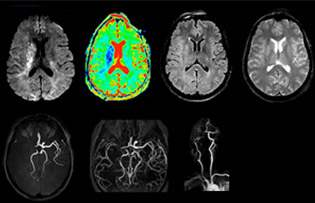

“Every center is different, but for me the ideal protocol for stroke includes diffusion weighted imaging, FLAIR, and fast susceptibility imaging,” says Dr. Savatovsky. “Our fast susceptibility weighted imaging takes 50 seconds, so it’s as fast as T2*-weighted imaging. It visualizes hemorrhage but also the clots. We also do 3D MR angiography that provides information on cervical and brain vessels. If the patient does not need immediate treatment, or if additional information is needed to decide on treatment, we might also add perfusion imaging and post-contrast T1-weighted imaging.”